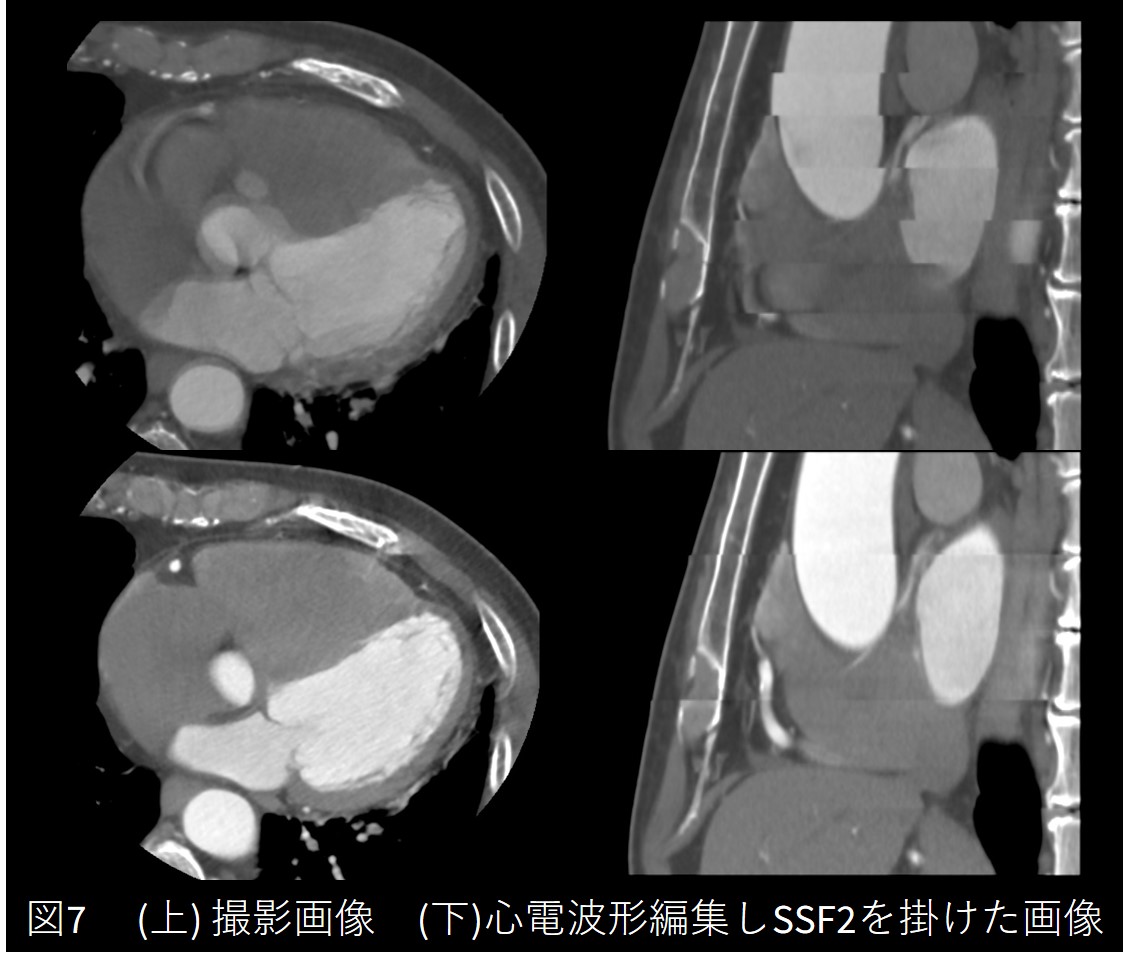

④PVC多発・息止め不良症例

冠動脈CT前のホルター心電図検査をしたところ、多源性PVC、連続した不整脈も多く見られ、撮影時も心室性期外収縮が多発しておりました。

撮影データを確認するとブレが大きく(図7(上))、検査終了後の副作用確認・説明の際に、造影検査時のみ息止めがほとんどできなかったといわれた症例です。

Frontier_Kofukyoritsu10.jpg

不整脈を削除した上で動きの少ない位相でSSF2を掛けたところ、図7(下)にまでバンディング影響を抑えることが出来ました。どうしてもバンディングの出てしまったLADは、より動きの少なかった別位相のデータで補完するなどの工夫で評価可能な画像を提出ことができました。

更新前の装置で撮影した際には、息止めができた検査でも冠動脈のブレが多く評価困難だったためカテーテル検査が必要になっていました。今回は息止め不良という悪条件が重なったにもかかわらず、CTのみで冠動脈の評価を行うことができました。